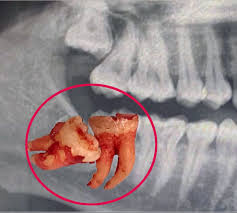

While some wisdom teeth fully erupt, others may partially emerge or fail to develop. Impacted wisdom teeth, which lack sufficient space to emerge properly, are a frequent issue.

Common Issues: Impaction, crowding, infection, or decay may necessitate removal.

Complications from an Impacted Tooth

Signs of Impaction: Pain, swollen gums, jaw discomfort, and headaches.